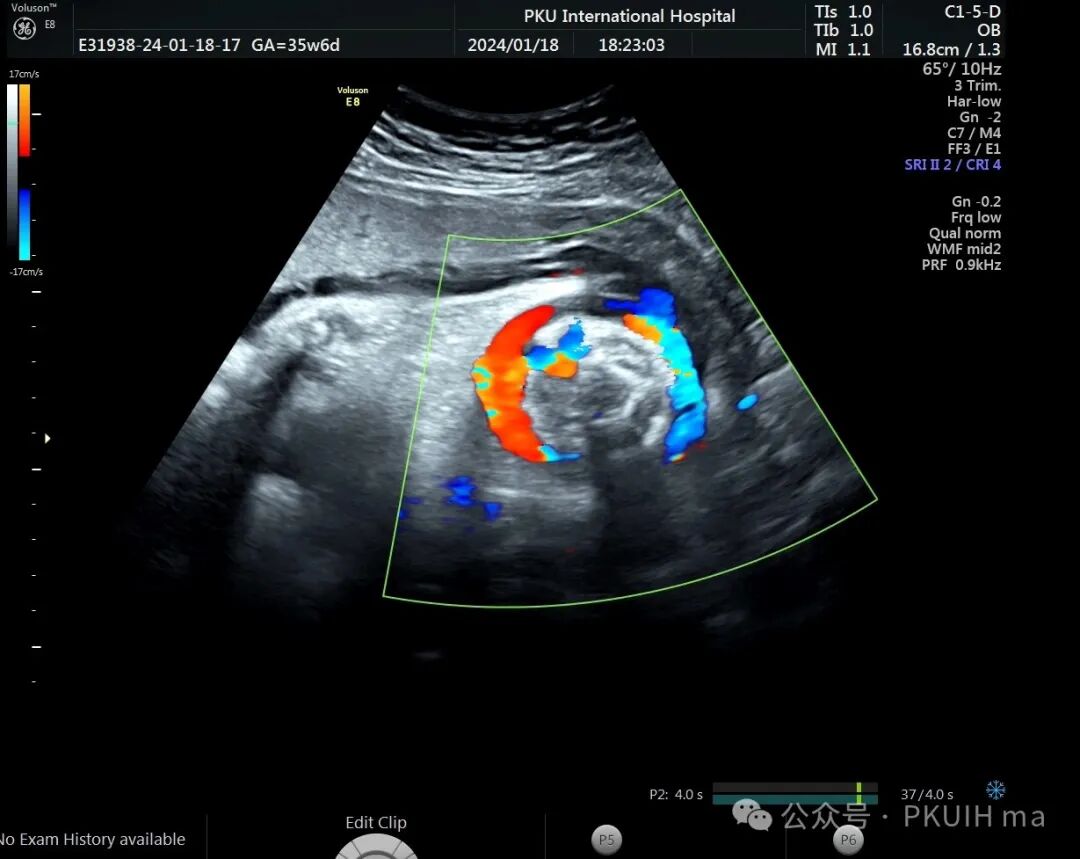

前两天碰到一孕妇胎动减少来诊,孕妇自述下午两点开始发现胎儿无明显胎动,吃了甜的食物和改变姿势还是不怎么动,随于下午六点左右来诊。超声发现胎儿绕颈两周以上且绕的较紧,检查中发现胎儿心率快,胎儿无明显胎动,绕颈处脐动脉血流加速时间延长,胎儿大脑中动脉阻力低,反复测量两侧大脑中动脉阻力均低。胎心监护也不好,随后产科采取紧急剖宫产。

脐带绕颈两周以上,绕的特别紧,感觉脖子都被勒细了,脐带与皮肤之间无任何空隙。绕颈处血流加速时间延长,说明可能存在交锁并出现了脐动脉局部狭窄